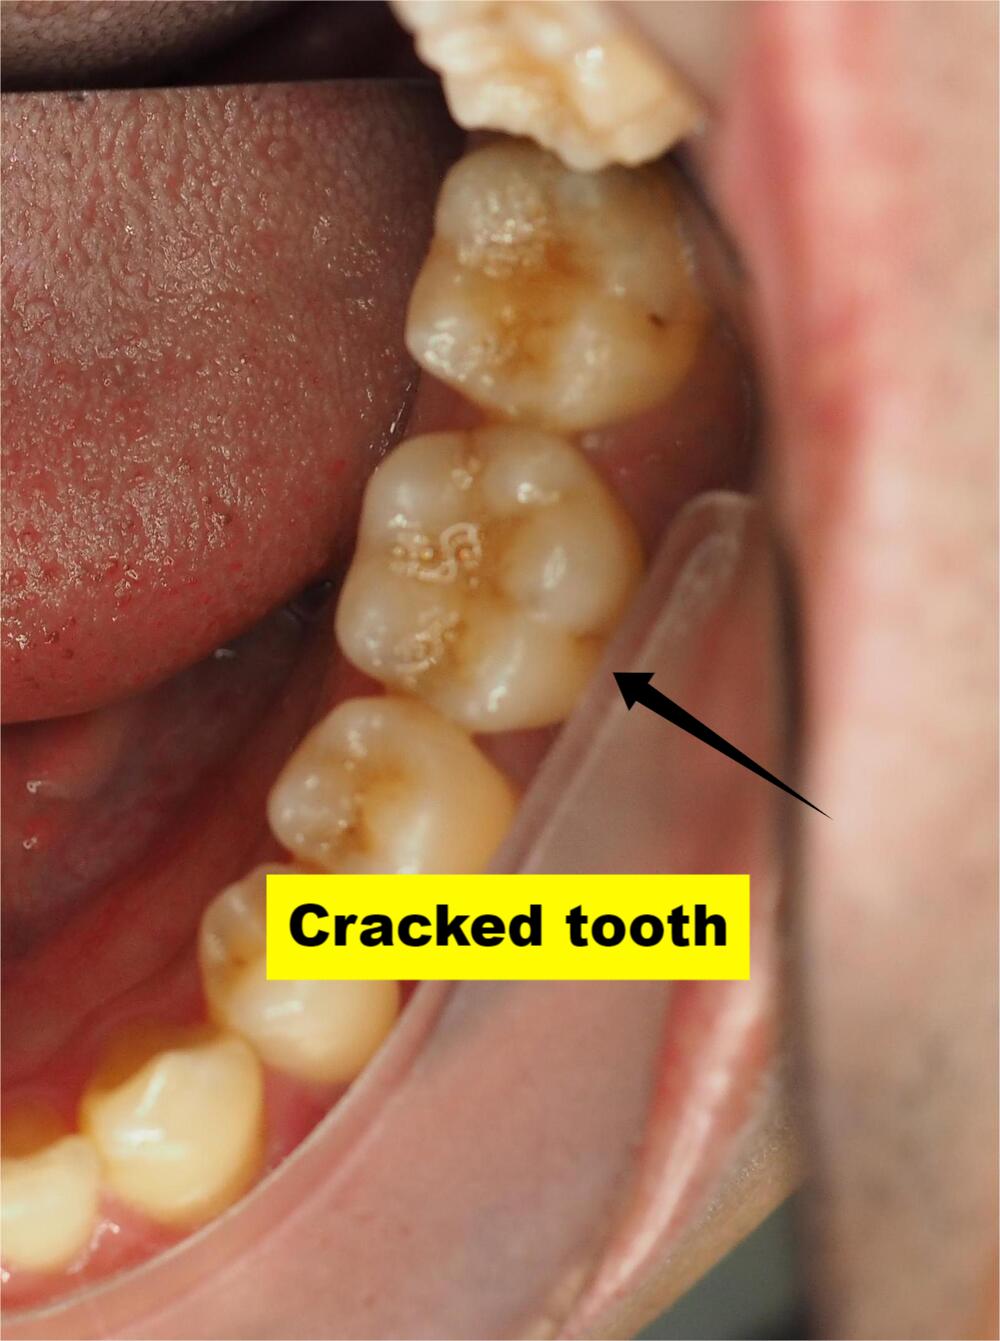

Extraction (If Needed) If the damaged tooth needs removal, we’ll do it carefully and plan implant placement after healing (typically 3 months).

Missing teeth don’t just affect how you look, they trigger bone loss that ages your face and makes future treatment harder and more expensive.

Let’s avoid that.

Actual patient results. Individual outcomes may vary.